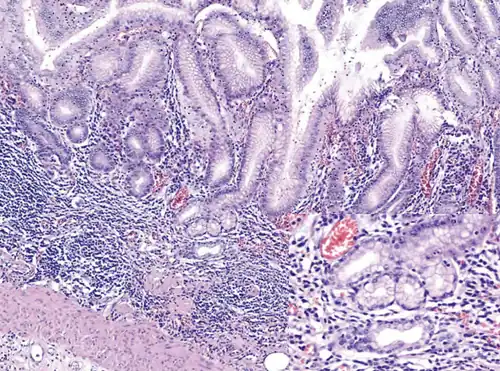

Atrophic gastritis under low power. H&E stain.